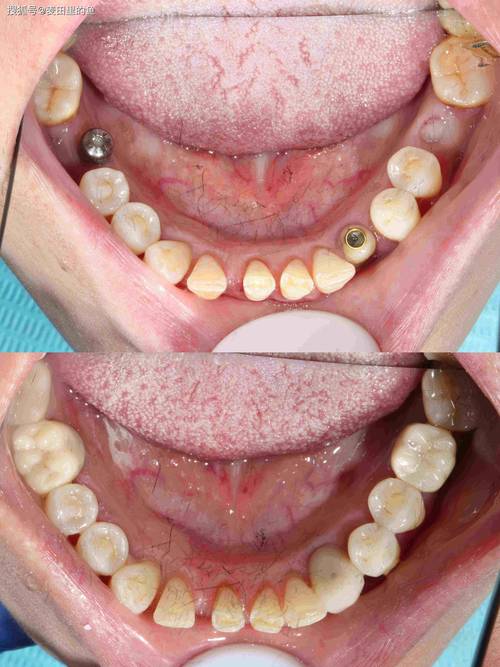

种植牙的原理是将人工牙根(种植体)植入牙槽骨内,让它与骨头牢固地结合(骨结合),从而为上面的牙冠提供稳定支撑,牙槽骨不足会带来以下问题:

现代口腔种植学已经发展出多种成熟的技术来解决牙槽骨不足的问题,核心就是“骨增量”或“骨增量同期种植”,这些技术旨在增加骨量、改善骨质量,为种植体创造一个稳固的“地基”。

如果之前尝试种植但因骨量不足而失败(例如种植体松动、脱落),或者评估后认为现有骨量无法支持种植,骨增量技术依然是首选的解决方案,失败的经历反而更清晰地表明了骨增量是必要的步骤。